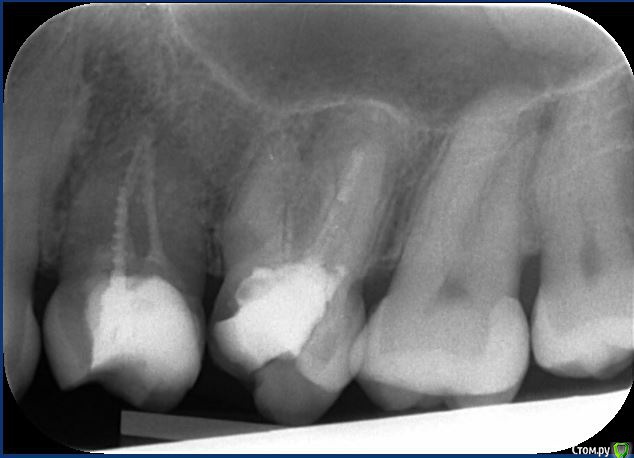

Елена67 Опубликовано 21 февраля, 2020 Поделиться Опубликовано 21 февраля, 2020 Уважаемые доктора, очень прошу вашего совета. На верхней челюсти на корне есть гранулема, периодически, не часто появляются ноющие боли. Пломба большая (на пол зуба), поставленная около 20 лет назад. Пролечить зуб никто не берется т. к неувены что могут пройти каналы. Советуют при обострениях принимать антибиотики или удалять зуб.Скажите пожалуйста можно ли спасти зуб, сделав резекцию корня в этом случае? Ссылка на комментарий